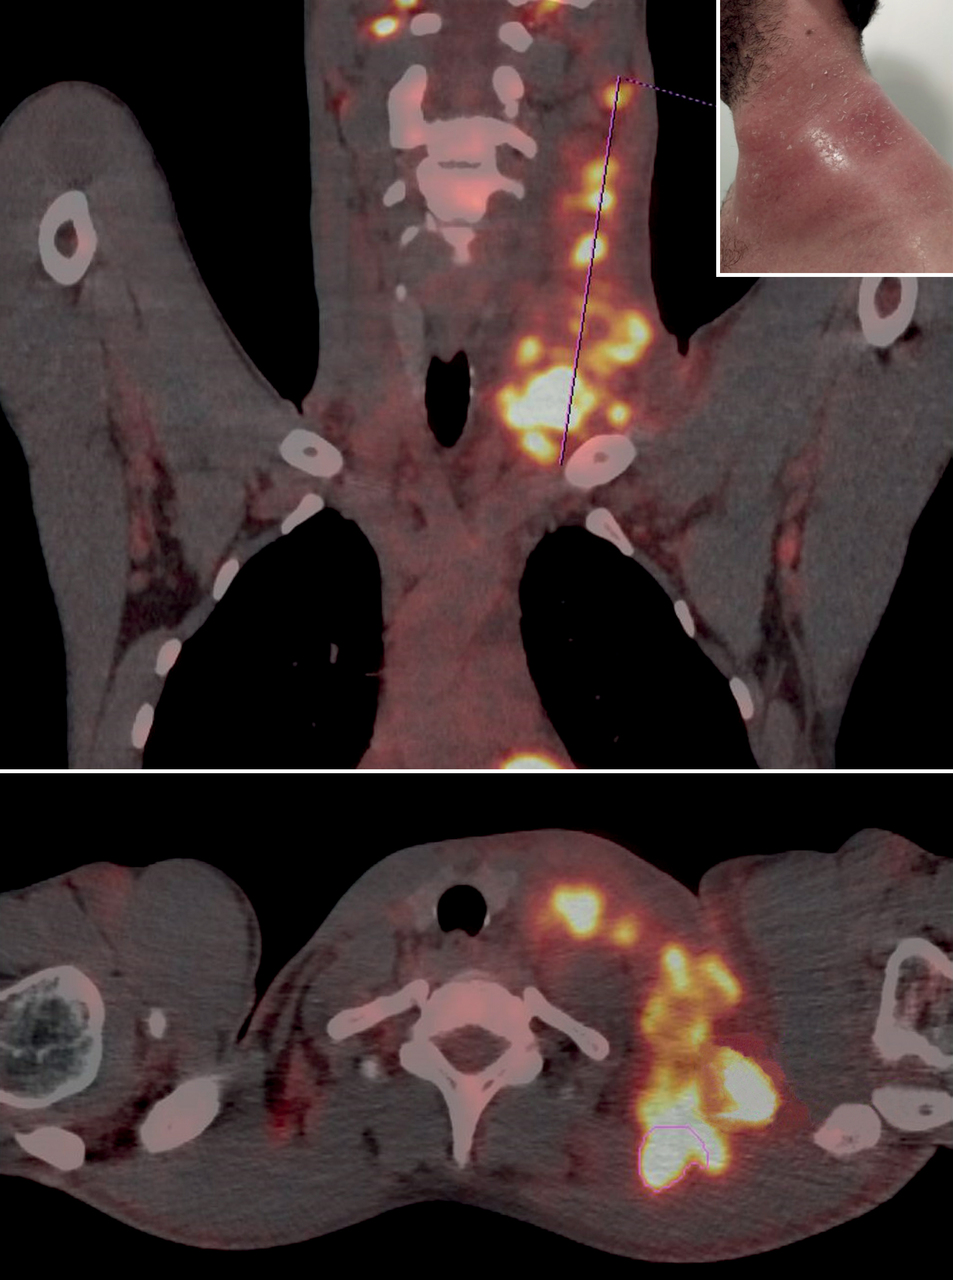

Un homme âgé de 25 ans est hospitalisé pour une fièvre à 39 °C évoluant depuis un mois, associée à une tuméfaction cervicale connue depuis quatre mois. Une TEP-TDM au 18-FDG est réalisée.

La tomographie par émission de positonstomodensitométrie (TEP-TDM au 18 FDG) montre un hypermétabolisme pathologique en regard d’une volumineuse infiltration tumorale ganglionnaire de fixation hétérogène cervicale gauche multiple, étendue dans le médiastin supérieur, en rétroclaviculaire gauche et en arrière du grill costal supérieur gauche avec inflammation sous-cutanée diffuse. La biopsie sous scanner n’est pas contributive. L’exérèse ganglionnaire ne permet pas de conclure entre un lymphome de Hodgkin peu cellulaire ou une localisation de lymphome T.